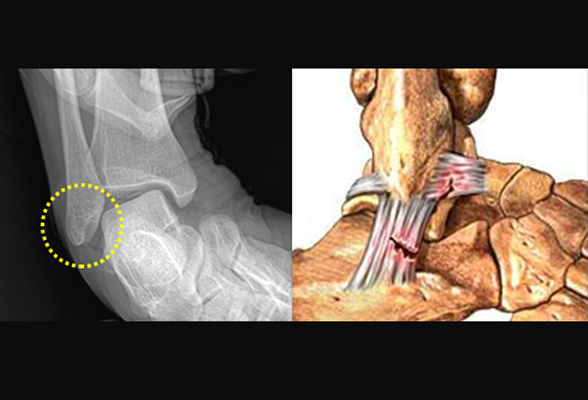

발목 연골 손상

발목 인대가 손상 되었을 때 치료를 하지 않고 그대로 방치하여 회복 되지 않거나

갑작스러운 외부의 충격으로 인해 연골 손상이 발생하며, 손상된 연골은 자연적인 재생이 불가능하여

반드시 재생 치료를 진행 해야 관절염으로 진행 되는 것을 예방 할 수 있습니다.

비수술 치료 : 약물, 고정치료 (깁스 또는 보조기), 물리치료, 주사치료, 도수치료

수술치료 : 발목 연골재생치료